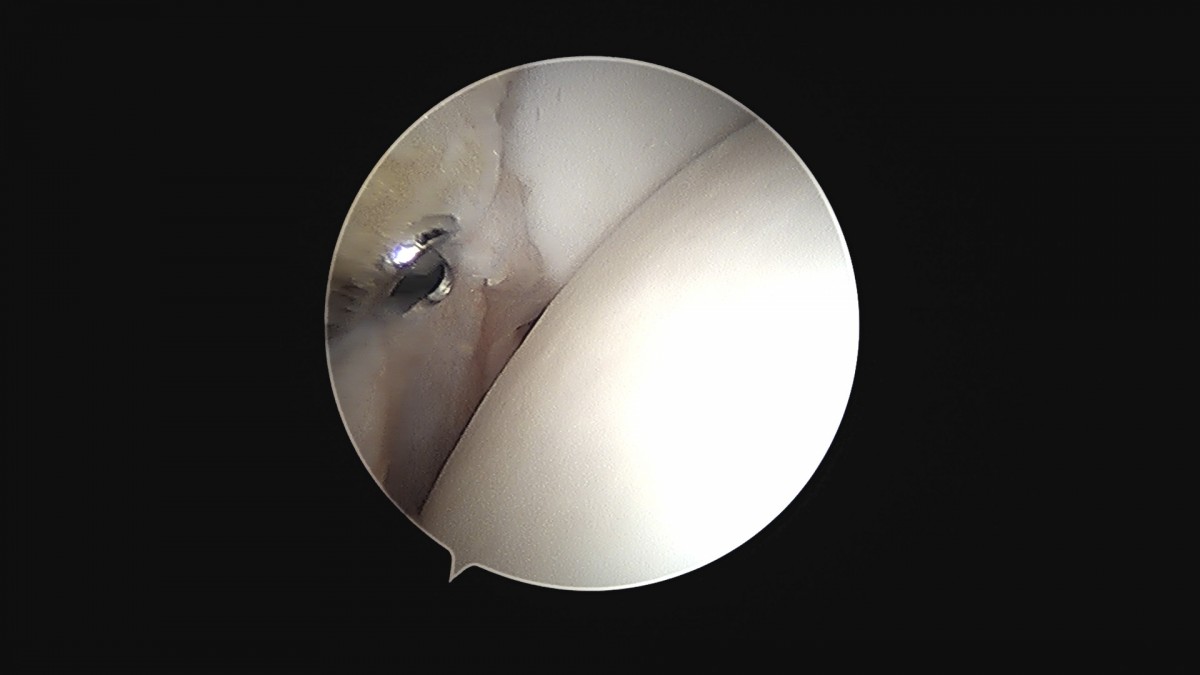

이재상원장님 발목 활액막 절제술 및 인대 봉합술 신진O 환자

dae765e4d9ac96aee867c9d6292d8784_1758003732_4452.jpg